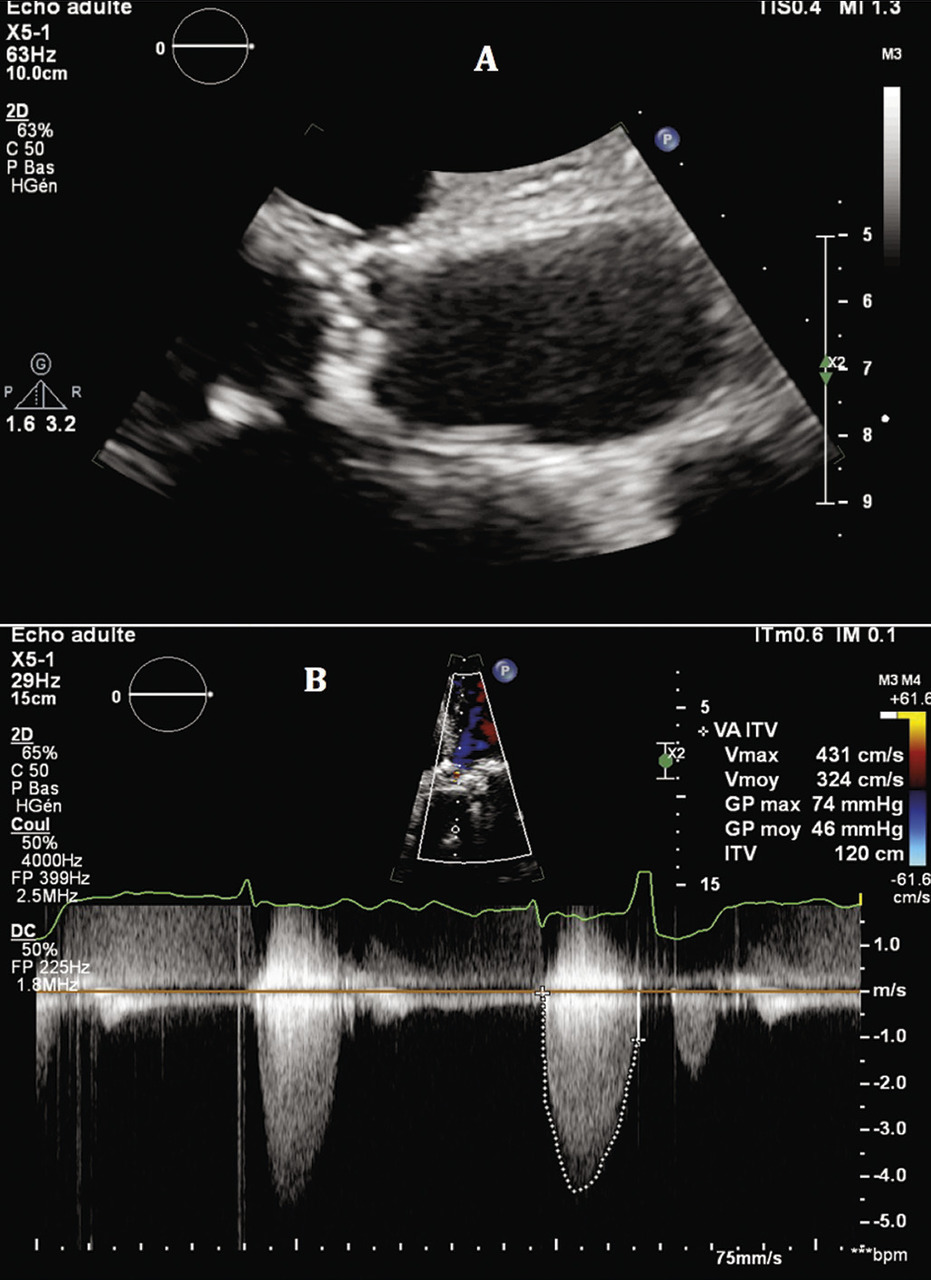

Diagnostic positif : on observe une valve aortique calcifiée dont l’ouverture est limitée, avec une accélération des flux en Doppler couleur (aliasing). Les vitesses sanguines à travers la valve sont augmentées (Vmax > 2,5 m/s) en Doppler continu (fig. 1).

Diagnostic de sévérité, quantification : un rétrécissement aortique est considéré comme serré, en présence d’un des critères suivants :

• Vmax ≥ 4 m/s (extrême si > 5,5 m/s) ;

• ou gradient moyen transvalvulaire ≥ 40 mmHg ;

• ou surface valvulaire aortique ≤ 0,6 cm2/m2 (ou < 1 cm2, mais la valeur indexée à la surface corporelle est préférée). Sachant qu’une surface valvulaire aortique normale est de l’ordre de 2 à 3 cm2.